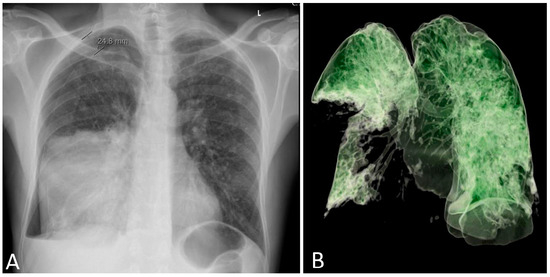

The patient’s clinical condition improved in the following days, and he continued to breathe spontaneously with oxygenation. The control chest radiograph of the lung revealed complete expansion of the lung parenchyma with lung infiltrates on the medial and lower lung lobes. The patient’s general condition gradually improved, and he was transferred to the ward on day 19 after ICU admission with supplemental oxygenation of 4 L O2/min via the nasal catheter and frequency of 18–20 breaths/minute with adequate oxygen saturation of 95–97%. The thoracic drain was removed on the ward (Figure 3).

Figure 3. A 3D computed tomography scan of the lungs 25 days after admission to the Intensive Care Unit. A: anterior, L: lateral.